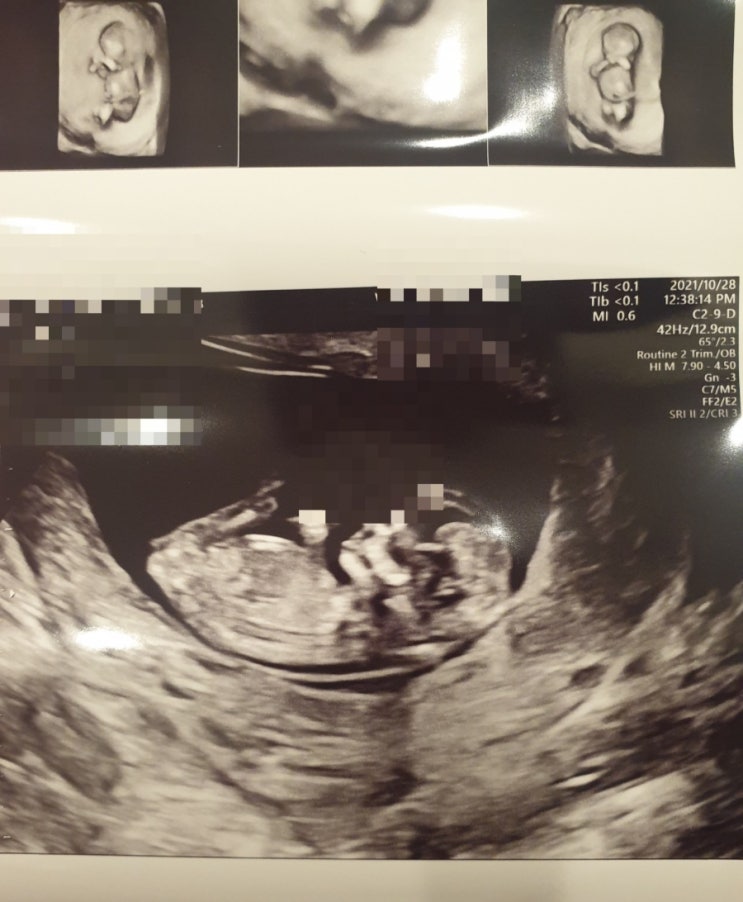

껀강이12주, 태교 자수

2021. 10.28 껀강이 12주 정밀초음파, 1차 기형아검사 완료! 목투명대 1.5 5.9cm 껀강이 건강하게 잘 커서 ...